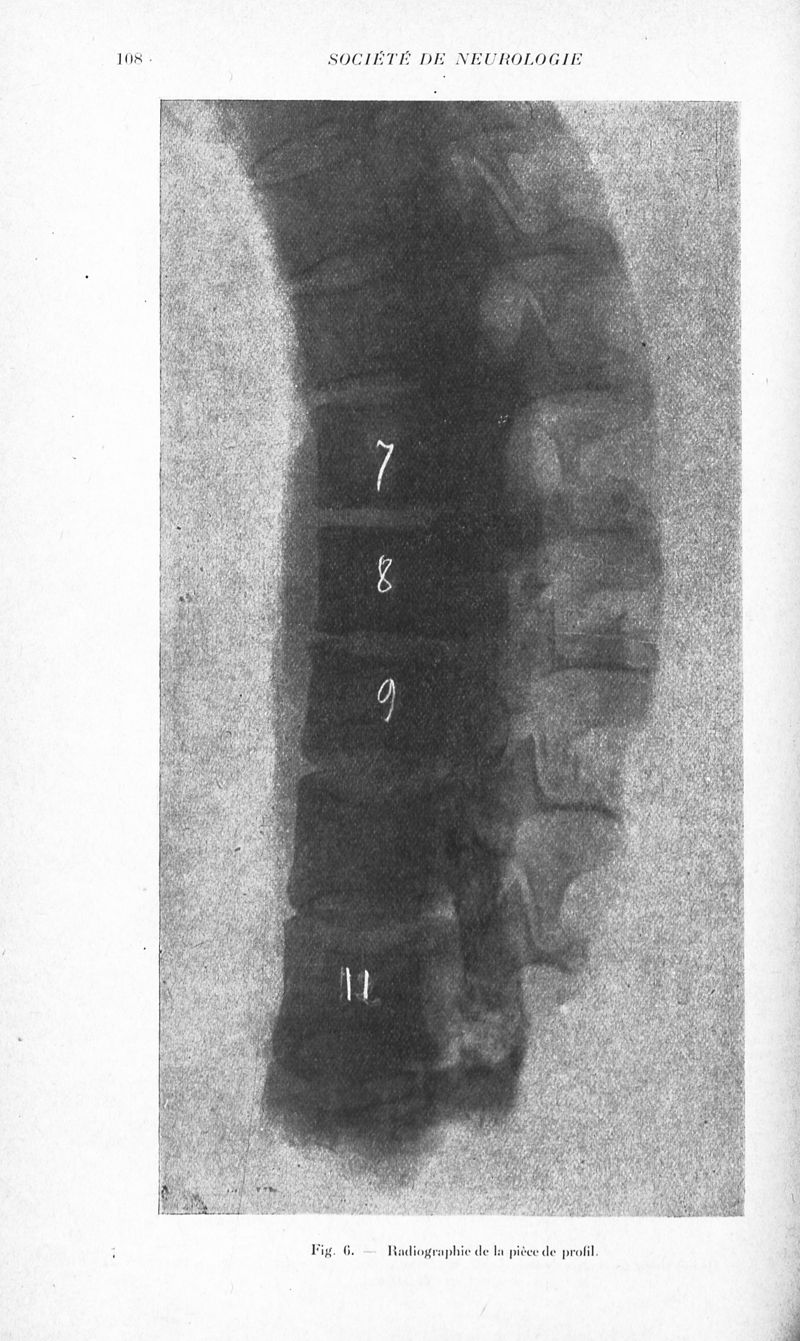

Revue neurologique

1925, vol 1. - Paris : Masson , 1925.